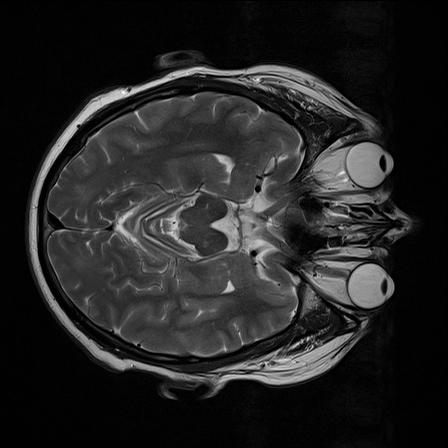

Ich arbeite an der Extraktion der Augen aus MR-Bildern (3D Daten) um im folgenden spezifische Paramter zu bestimmen (Groesse, Volumen...) und sie letztendlich als 3D Modell darzustellen. Leider ergeben sich oftmals durch den schwachen Kontrast zwischen dem Auge und dem umliegenden Gewebe Probleme das Auge korrekt zu extrahieren (z.B. mittels 'region growing').

Leider wird allerding in der Regel wird keine geschlossene Kontur (um das Auge) erkannt, was bei dem folgendem 'region growing algorithmus' dazu fuehrt, dass er ueber das Auge hinaus geht. Zu besseren Vorstellung habe ich ein Originalbild und das Bild nach der Kantendetektion mit angehangen.

Meine Frage waere also, ob es eine Moeglichkeit gibt die 'Loescher' in den Kanten zu schliessen (wobei ich noch nicht wirklich weiss wie ich die Datenpunkte der Kanten die zum Auge gehoeren bestimmen kann, die fuer eine Approximation wohl notwendig waeren) oder vielleicht den Kontrast zwischen Auge und umgeben Gewebe so zu verbessern, dass die Kanbtendetektion immer eine geschlossene Kontur ausgibt.